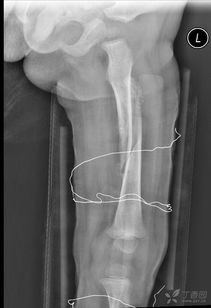

我們知道,這些微量元素是形成和發(fā)育骨骼的重要成分。另外在治療期間可以進行物理方面的治療與護理,如按摩,讓患處的血液循環(huán)變得好起來,這對于打著鋼板的患處是很有好處的,預防因長時間不活動導致的肌肉萎縮現(xiàn)象的發(fā)生。